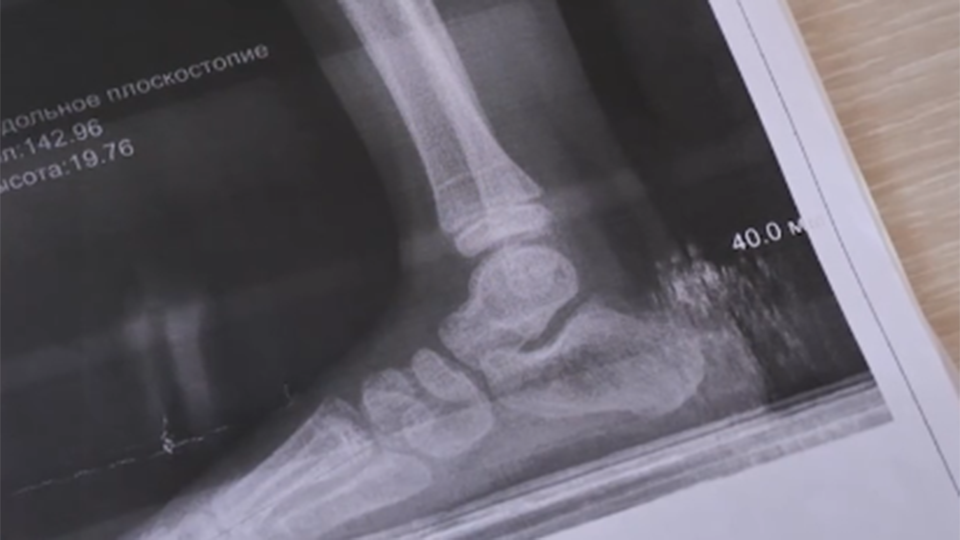

"У ребенка адские боли, он кричит, он умоляет: "Мама, помоги". И мой ребенок кричал: "Она меня хотела убить". Это то, что я запомнила. Очень сильно он это кричал. Ребенка забрали на операцию. У него был перелом двух костей голени со смещением, проводилась операция под наркозом", – поделилась подробностями мать пострадавшего Наталья Кошкина.

Операция длилась больше часа. Прошла успешно, но врачи не могут точно сказать, сможет ли ребенок восстановиться полностью.